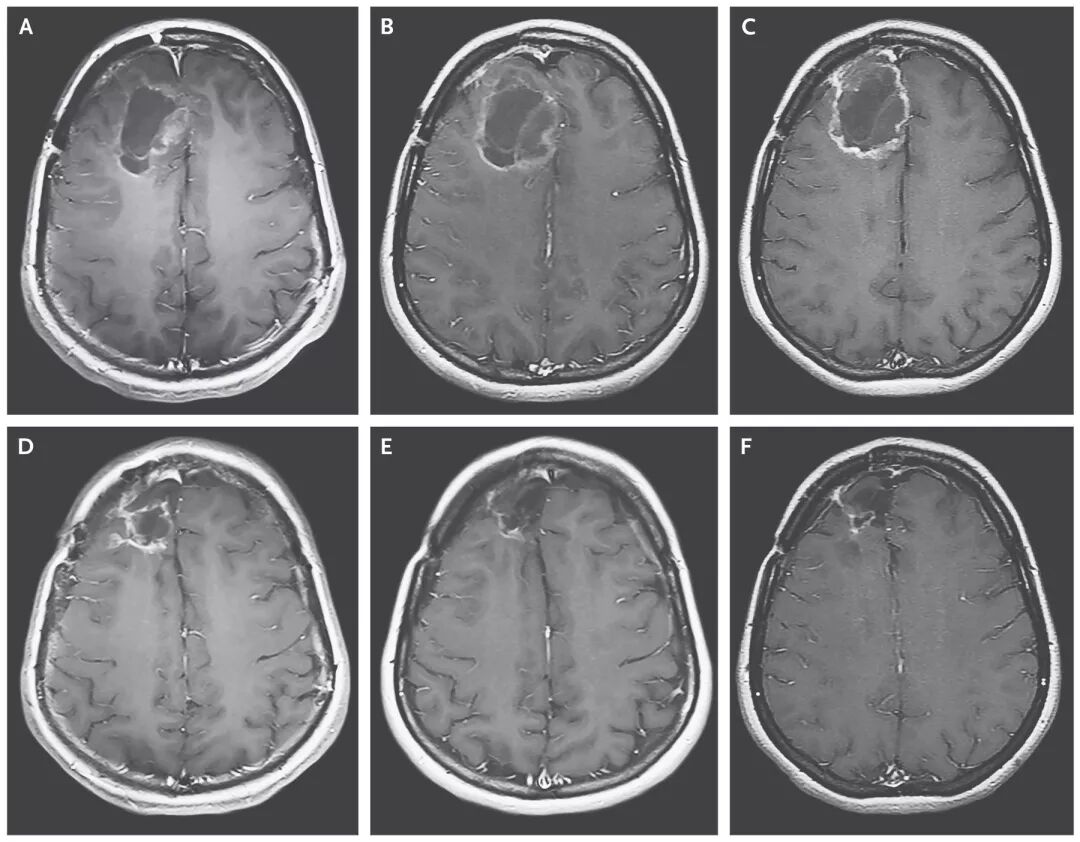

图1. 给予溶瘤病毒后的MRI影像学表现。A.MRI显示接受剂量1(108 TCID50)的PVSRIPO时肿瘤大小;B.PVSRIPO输注2个月后肿瘤扩张;C.输注6个月后肿瘤有所缩小;图D和E分别为给PVSRIPO后12个月和24个月时的结果;F.输注病毒后58个月时的肿瘤残余腔,显示肿瘤缩小。

2012年5月至2017年5月,61例患者入组并接受至少一剂PVSRIPO。将剂量-1(5.0×107 TCID 50)定为剂量递增阶段的初始剂量。在此阶段,作者观察到剂量限制性毒性作用,即给药剂量为5(1010 TCID50)的患者在给药导管拔除后立即出现4级颅内出血。在剂量扩张阶段,19%患者有3级或以上与PVSRIPO相关的不良并发症。接受PVSRIPO治疗的患者在36个月时总体生存期达到21%(95% CI,11~33个月),对照组仅为4%(图1)。没有任何因素可以预测持续缓解的患者是属于哪种亚型。93%以上的毒性属于1级或2级。在10%以下患者中观察到偏瘫、头痛和癫痫发作等的3级毒性反应。